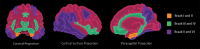

Neurodegenerative diseases are a devastating group of disorders that can be difficult to accurately diagnose. Although these disorders are difficult to manage owing to relatively limited treatment options, an early and correct diagnosis can help with managing symptoms and coping with the later stages of these disease processes. Both anatomic structural imaging and physiologic molecular imaging have evolved to a state in which these neurodegenerative processes can be identified relatively early with high accuracy. To determine the underlying disease, the radiologist should understand the different distributions and pathophysiologic processes involved. High-spatial-resolution MRI allows detection of subtle morphologic changes, as well as potential complications and alternate diagnoses, while molecular imaging allows visualization of altered function or abnormal increased or decreased concentration of disease-specific markers. These methodologies are complementary. Appropriate workup and interpretation of diagnostic studies require an integrated, multimodality, multidisciplinary approach. This article reviews the protocols and findings at MRI and nuclear medicine imaging, including with the use of flurodeoxyglucose, amyloid tracers, and dopaminergic transporter imaging (ioflupane). The pathophysiology of some of the major neurodegenerative processes and their clinical presentations are also reviewed; this information is critical to understand how these imaging modalities work, and it aids in the integration of clinical data to help synthesize a final diagnosis. Radiologists and nuclear medicine physicians aiming to include the evaluation of neurodegenerative diseases in their practice should be aware of and familiar with the multiple imaging modalities available and how using these modalities is essential in the multidisciplinary management of patients with neurodegenerative diseases.©RSNA, 2020.